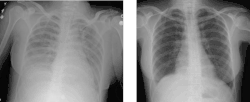

Die TRALI ist definiert als akute Atemnot, die innerhalb von sechs Stunden nach einer Bluttransfusion auftritt, mit Lungeninfiltraten (Lungenödem) in der Röntgenaufnahme des Thorax und ohne Anzeichen für eine Herzinsuffizienz infolge einer Volumenüberladung als Ursache.[1]

TRALI äußert sich typischerweise als akut auftretende Atemnot (Dyspnoe), häufig von Blutdruckabfall (Hypotonie) und Fieber begleitet. Im Röntgenbild des Brustkorbes (Röntgen-Thorax) können erhebliche Infiltrate infolge des Lungenödems auftreten, die oft in Diskrepanz zum klinischen Bild stehen. Oft findet sich auch ein Abfall der Leukozyten im Blutbild.[2]

Die Diagnose ergibt sich aus klinischem Bild im Zusammenhang mit einer Transfusion und der Röntgen-Thorax-Aufnahme. Bei der wichtigsten Differenzialdiagnose, dem kardiogenen Lungenödem aufgrund einer Überlastung des Kreislaufes durch das Transfusionsvolumen (transfusion-associated circulatory overload, TACO), ist oft die linksventrikuläre Pumpfunktion eingeschränkt (Echokardiographie), die Herzsilhouette verändert (Röntgen-Thorax) und das Brain Natriuretic Peptide erhöht.